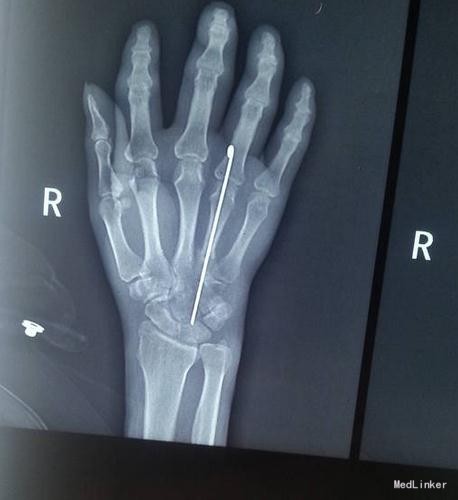

入院12天后,在臂丛麻醉下行切开复位内固定术。完全愈合伤口,并拆线出院。后因肿胀又入我科治疗,先后给予中药外敷 硫酸镁湿敷 中医理疗等 不见好转。 查血常规在正常范围之内。将内固定拔出,红肿严重广泛于手背下,有种象皮肿的感觉,未形成脓肿。

红肿已经局限于腕背部。药物给予头孢噻肟2.0g bid ivgtt 左氧氟沙星注射液 200ml,ivgtt qd 庆大霉素 24万单位 ivgtt qd.